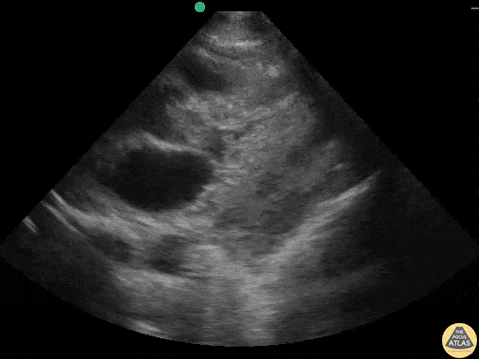

59 y/o F PMH metastatic squamous cell carcinoma of lung with metastases to bone, brain, liver, subcutaneous tissue presents with undifferentiated SOB. Patient tachycardic, hypotensive but alert with EKG showing non-sustained ventricular tachycardia. Multiple hypodensities and cystic lesions in the LV, proximal outflow tract in left ventricle, all suggestive of a thrombus vs mass vs vegetations. Eventual presumed diagnosis after formal transthoracic echo is metastases to the heart. Dr. Joshua Schecter, Dr. John F. Kilpatrick - Kings County/SUNY Downstate Emergency Medicine